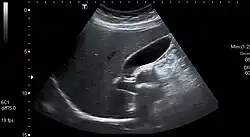

Gallstones are diagnosed using ultrasound.[20] When a symptomatic gallstone occurs, it is often managed by waiting for it to be passed naturally; however, given the likelihood of recurrent gallstones, surgery to remove the gallbladder is often considered.[21] Some medication, such as ursodeoxycholic acid, may be used; lithotripsy, a non-invasive mechanical procedure used to break down the stones, may also be used.[21]

An ultrasound scan is often the first medical imaging test performed when gallbladder disease, such as gallstones, is suspected.[21] An abdominal X-ray or CT scan is another form of imaging that may be used to examine the gallbladder and surrounding organs.[21] Other imaging options include MRCP (magnetic resonance cholangiopancreatography), ERCP (endoscopic retrograde cholangiopancreatography), and percutaneous or intraoperative cholangiography.[21] A cholescintigraphy scan is a nuclear imaging procedure used to assess the condition of the gallbladder.[28]